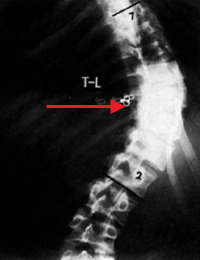

و كذلك بالأشعة يمكن معرفة ما إذا كان الجنف (الإنحناء) بنيوي أو مُعاوض (تعويضي) Compensatory Curvature , الإنحناء المُعاوض يحدث نتيجة للإنحناء البنيوي ليتوازن الجسم. تُأخذ صورة أشعة للشخص و هو منحني جانبياً لليمين و أخرى و هو منحني جانبياً لليسار, مما يؤدي إلى إختفاء الإنحناء المُعاوض و لكن الإنحناء البنيوي يظل. و هذه الطريقة كذلك تفيد في معرفة مرونة العمود الفقري لدى المريض.

في الصورة, في حال الوقوف الجنف يكون صدري قطني أيسر, عند الإنحناء يساراً لا يختفي الإنحناء الصدري لأنه بنيوي , و لكن عند الإنحناء يميناً يختفي الإنحناء القطني مما يعني بأنه مُعاوض و ليس بنيوي.

الفقرات باللون الأحمر = الفقرات الصدرية و الفقرات باللون الأصفر= الفقرات القطنية.